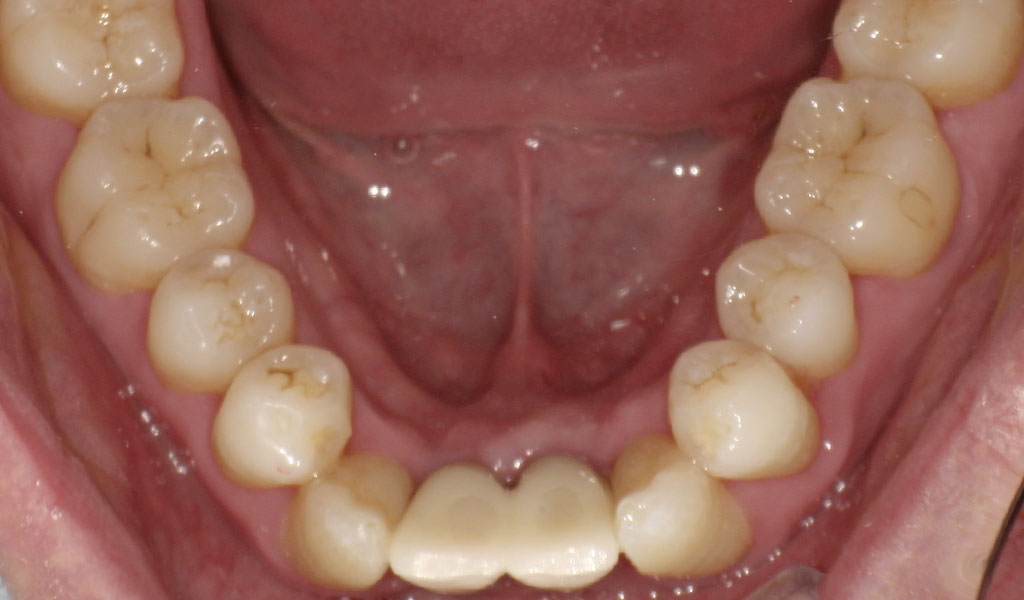

After1

After2

インプラントと骨がしっかり結合するまで3ヶ月待ち、また、歯周内科による治療が終わった上で、インプラントの上に人工の歯を被せる治療を行いました。